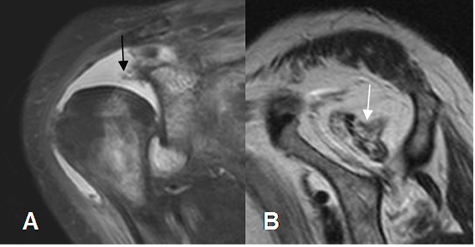

Fig 29 A. Atrofia Muscular.

A: RM coronal en STIR. Ruptura retraída del tendón supraespinoso.

B: RM sagital en T1.El músculo supraespinoso en atrófico y con alteración de su señal, por degeneración grasa, secundario a una ruptura de evolución crónica.